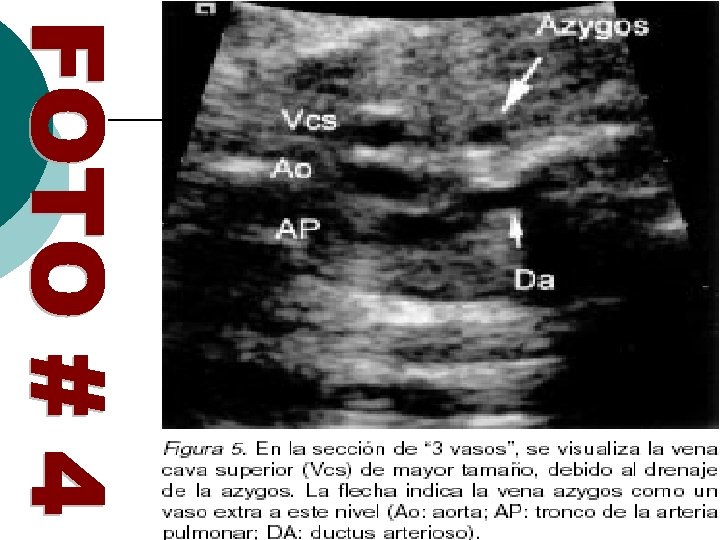

EN LA VISIÓN DE 3 VASOS A NIVEL DE MEDIASTINO SUPERIOR SE ORDENAN EN CONDICIONES NORMALES DE IZQUIERDA A DERECHA: EL TRONCO DE LA PULMONAR. AORTA ASCENDENTE. VENA CAVA SUPERIOR QUE ES DE MENOR TAMAÑO QUE LA AORTA ASCENDENTE. CUANDO LA V. C. I ESTA INTERRUMPIDA Y EL RETORNO ES POR LA AZIGOS ESTA DESEMBOCA A NIVEL DE LA CAVA SUPERIOR Y EL TAMAÑO SERÁ MAYOR QUE EN CONDICIONES HABITUALES VER FOTO # 4